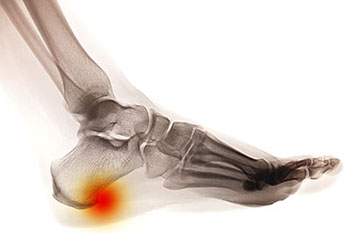

Heel spurs are brought upon by a calcium deposit that causes a bony protrusion on the underside of the heel bone. It normally forms over time and can best be diagnosed through an x-ray examination. Heel spurs are commonly linked with plantar fasciitis, an inflammation that runs along the bottom of the foot. Common symptoms of heel spurs include pain towards the affected area, inflammation, and swelling at the front of the heel.